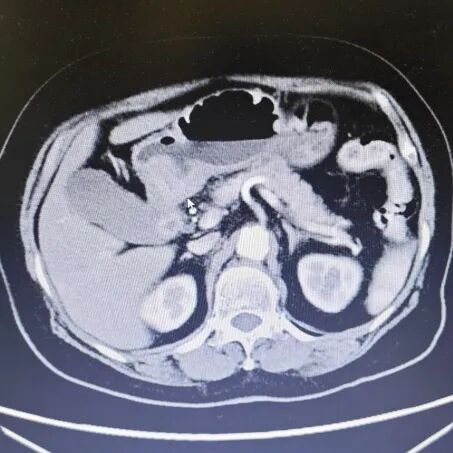

内容提要 近日,在葫芦岛市第二人民医院胃肠外科主任、原锦州医科大学附属医院胃肠外科主任乔世峰教授主刀下,成功为一位73岁的高龄胃癌患者实施了高难度胃远端切除术伴胃-十二指肠吻合术(毕Ⅰ式),充分彰显了乔世峰主任在胃肠道肿瘤外科领域深厚的技术功底与丰富经验。 1 高难手术,助力快速康复 李奶奶今年3月在外院被确诊为(胃窦-胃角)恶性肿瘤,辗转到我院寻求进一步手术治疗。考虑到患者年龄较大、病灶位置复杂,乔世峰主任在术前全面评估后,决定采用胃远端切除术伴胃-十二指肠吻合术。 肠镜及病理结果 该术式属于四级手术,技术要求高,但对患者术后生活质量有明显优势:在完整切除肿瘤、系统清扫周边淋巴结的同时,保留十二指肠原有生理位置,行胃后壁与十二指肠端侧吻合(毕Ⅰ式),吻合后更符合人体正常消化通路,术后并发症少,恢复更快。 乔世峰主任凭借40余年胃肠外科临床经验,携张凯副主任及团队成员,从容完成肿瘤完整切除及淋巴结清扫,确保根治效果。随后,精准实施胃后壁与十二指肠端侧吻合,吻合通畅、血供良好,整个手术过程平稳。术后患者消化功能恢复快,并发症发生率显著降低,生活质量更高。 胃部影像(鼠标所指为病变处) 此次高难度手术的成功实施,再次体现了我院在复杂胃肠外科治疗中的技术实力。乔世峰教授深耕临床多年,在胃肠道肿瘤的规范化治疗及疑难病例诊疗等方面有着深厚的造诣和丰富的临床经验,尤其擅长各类腹腔镜胃肠肿瘤根治术,致力于为患者提供创伤更小、恢复更快、根治更彻底的诊疗服务。 随着乔世峰教授的加盟,我院胃肠外科的学科建设和诊疗能力迈上了新台阶。未来,科室将在乔世峰主任的带领下,持续深耕技术创新,不断优化诊疗服务,全力提升胃肠道肿瘤及疑难重症的诊治水平。 2 人民医院 人民名医 乔世峰 博士后 主任医师 教授 硕士研究生导师 ·葫芦岛市第二人民医院胃肠外科主任 ·原锦州医科大学附属第一医院胃肠外科主任 ·首都医科大学医学博士、天津医科大学博士后 ·辽宁省医学会外科分会疝与腹壁外科学组委员 ·辽宁省医学会肠外肠内营养学会委员 ·东北三省肠外肠内营养支持专业委员会委员 ·辽宁省中西医结合学会肿瘤专业委员会常委 ·《中国肿瘤生物治疗杂志》特约审稿专家 专业特色:省内胃肠外科领域领军专家,从事普外科工作近40年,擅长胃肠道多发、疑难病诊治,精通普外科各类手术,如胃癌、结肠癌、疝、肠梗阻、肝癌、胆囊切除术、胰腺手术等。深耕胃肠道肿瘤规范化治疗与微创技术创新,在省内较早开展腹腔镜微创胃肠肿瘤手术,具有极高造诣。在国家核心期刊发表学术论文20余篇,SCI论文10余篇。 出诊时间:每周三全天 咨询热线:0429-8010259 张凯 副主任医师 硕士研究生 ·葫芦岛市第二人民医院胃肠外科副主任 ·辽宁省生命科学学会胃肠肿瘤专业委员会委员 ·中医临床药学分会委员理事 ·沈阳市抗癌协胃癌专业委员会委员 专业特色:以腹部外科为诊治方向,擅长普通外科多发及疑难病的诊断、治疗和手术。以微创技术为特色优势,擅长腹腔镜阑尾切除术、腹股沟疝修补术、结直肠癌根治术、胃癌根治术。先后发表论文2篇,完成“腹腔镜、胆道镜及两镜联合手术临床应用”科研项目,并获得了葫芦岛市科学技术成果奖励二等奖,学术论文类获得葫芦岛市自然科学学术成果一等奖。